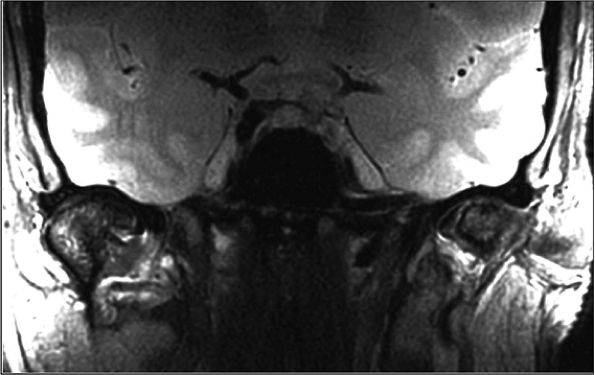

FIGURE 1.26 ● Hip examination, coronal fast spin-echo proton density-weighted image with FatSat (TR 3100, TE 41). (A) Images acquired with a four-channel cardiac array coil. (B) Images acquired with a body coil. The signal-to-noise improvement with the array coil is at least 100%.

|